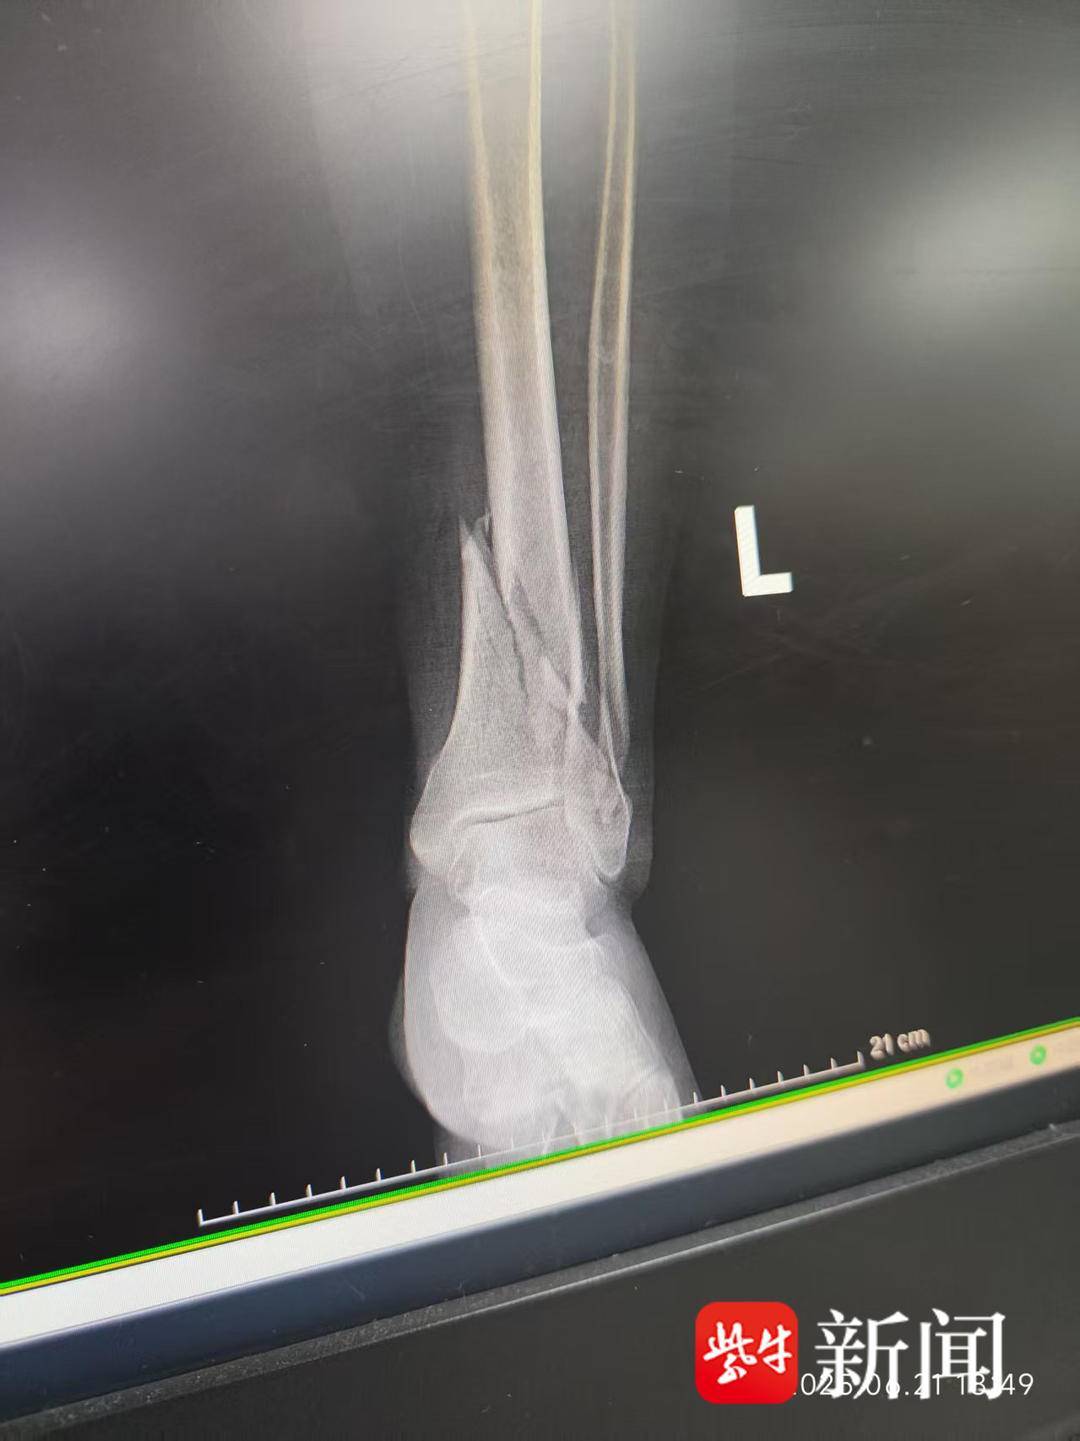

就在南京队员和球迷都沉浸在客场四球大胜常州队的喜悦中时,扬子晚报/紫牛新闻记者得知了一条伤心的消息,记者的好友——南京铁杆球迷会会长李成在赛前组织安排球迷入场时,因为雨天湿滑,小腿部意外骨折。

李成腿部骨折

赛后,当记者向他询问本场球迷的组织工作时,李成给记者发来了一张医院天花板的照片,在记者的再三追问下,他才说明了自己腿部骨折的情况。一场盛大的足球赛事成功举办,离不开千千万万人的努力,更离不开工作人员、球迷等默默地付出。